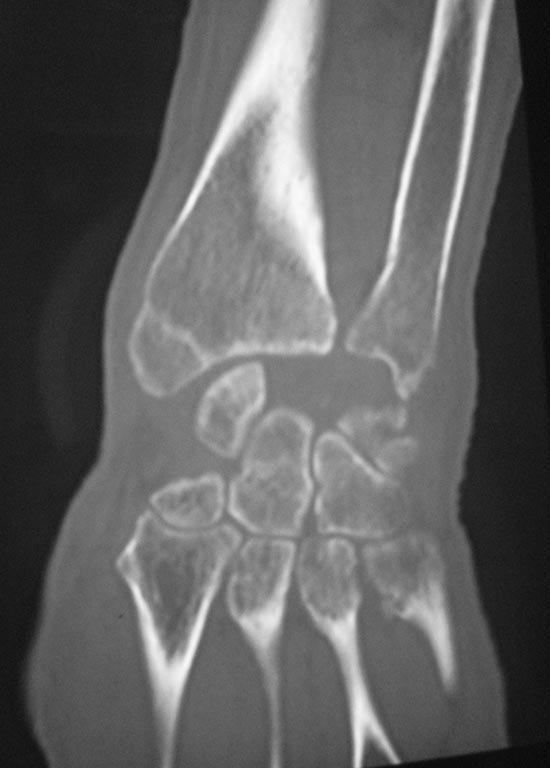

[Ortho] Застарелый вывих полулунной кости

Вот КТ